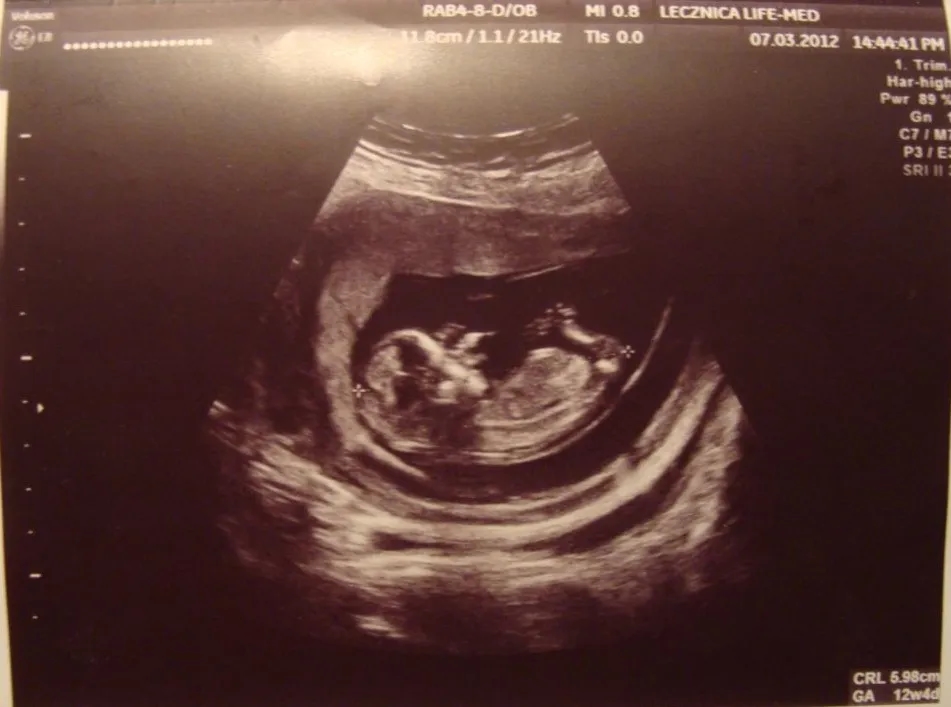

Jakie informacje można uzyskać z badań ultrasonograficznych?

Badania ultrasonograficzne w 13 tygodniu ciąży dostarczają cennych informacji o zdrowiu płodu i jego rozwoju. Ultrasonografia pozwala na ocenę wielkości płodu, co jest istotne dla określenia, czy rozwija się on zgodnie z oczekiwaniami. Można również zobaczyć, jak rozwijają się jego narządy wewnętrzne oraz zewnętrzne cechy, takie jak kształt głowy czy długość kończyn. Ponadto, badanie to umożliwia wykrycie ewentualnych nieprawidłowości, co jest kluczowe dla wczesnej interwencji w przypadku wykrycia problemów.

Ultrasonografia jest również ważna dla potwierdzenia daty porodu, co pozwala na lepsze planowanie opieki prenatalnej. Dzięki tym badaniom rodzice mogą zobaczyć swojego maluszka i zyskać pierwsze wyobrażenie o tym, jak wygląda ich dziecko. To doświadczenie może być emocjonujące i pełne radości, a także dostarcza informacji, które są nieocenione dla zdrowia matki i dziecka.